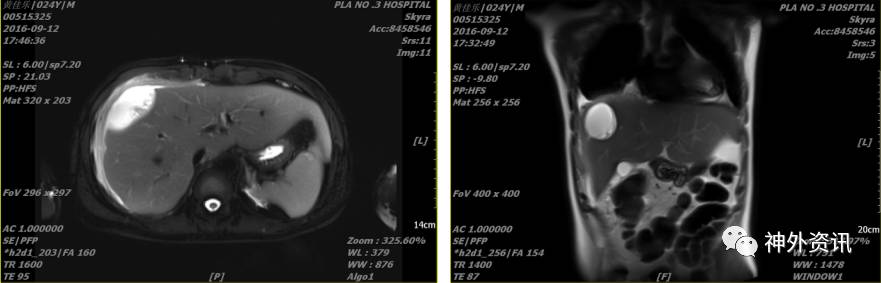

患者于2016-08-27出现发热,伴咳嗽,白细胞(WBC)16.67×109/L、中性细胞比率(NE%)87.8%、中性细胞计数(NE)14.6×109/L、降钙素原测定(PCT)0.45ng/ml、超敏C反应蛋白测定(UsCRP)35.20mg/L,给予舒普深静滴后,2016-08-30复查血常规:白细胞(WBC)6.76×109/L、中性细胞比率(NE%)57.4%、超敏C反应蛋白测定(UsCRP)4.10mg/L、降钙素原测定(PCT)0.05ng/ml,2016-09-02体温恢复正常,停用舒普深, 2016-09-10再次出现发热, 体温38.6度,患者出现腹痛,2016-09-12腹部B超及MRI示:腹腔包裹性积液、双侧胸膜腔少量积液。2016-09-13日查胸部CT示:1.双肺下叶渗出性改变伴右肺下叶部分不张,2.双侧胸膜腔积液,以右侧为著。请呼吸科、胸外科会诊后,行胸腔闭式引流,血培养未见异常,胸水生化提示感染性渗出性改变。

2016-09-12行胸部超声后,复查腹部MRI示(2016-12-12 17:46):

2016-09-13复查胸部CT示:

胸外科2016-09-13给予胸腔闭式引流,当日引出淡黄色胸水约600ml,送化验示:淡黄色浑浊胸水,白细胞手工计数1363.00×106/L、胸腹水糖(XGLU) 5.43mmol/L、胸腹水蛋白46.60、普通培养无细菌生长,考虑渗出液,肺部感染及胸腔积水。第二日复查胸部CT示(2016-12-04 10:50):